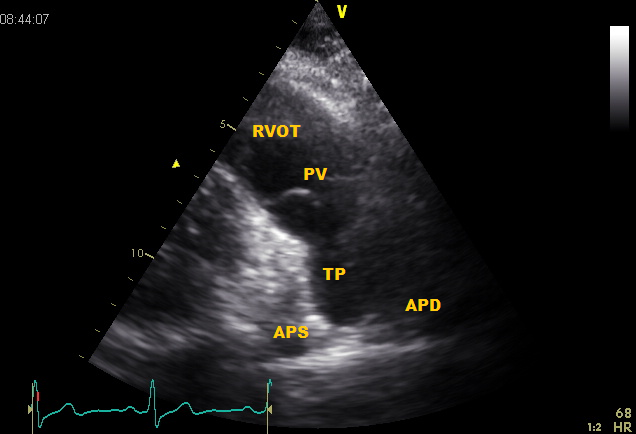

Pulmonary level

From PLAX tilt to cranial. This is a great image for the Pulmonary valve (PV), pulmonary artery, including the pulmonary trunk (TP) which splits into the right (APD) and left pulmonary artery (APS).